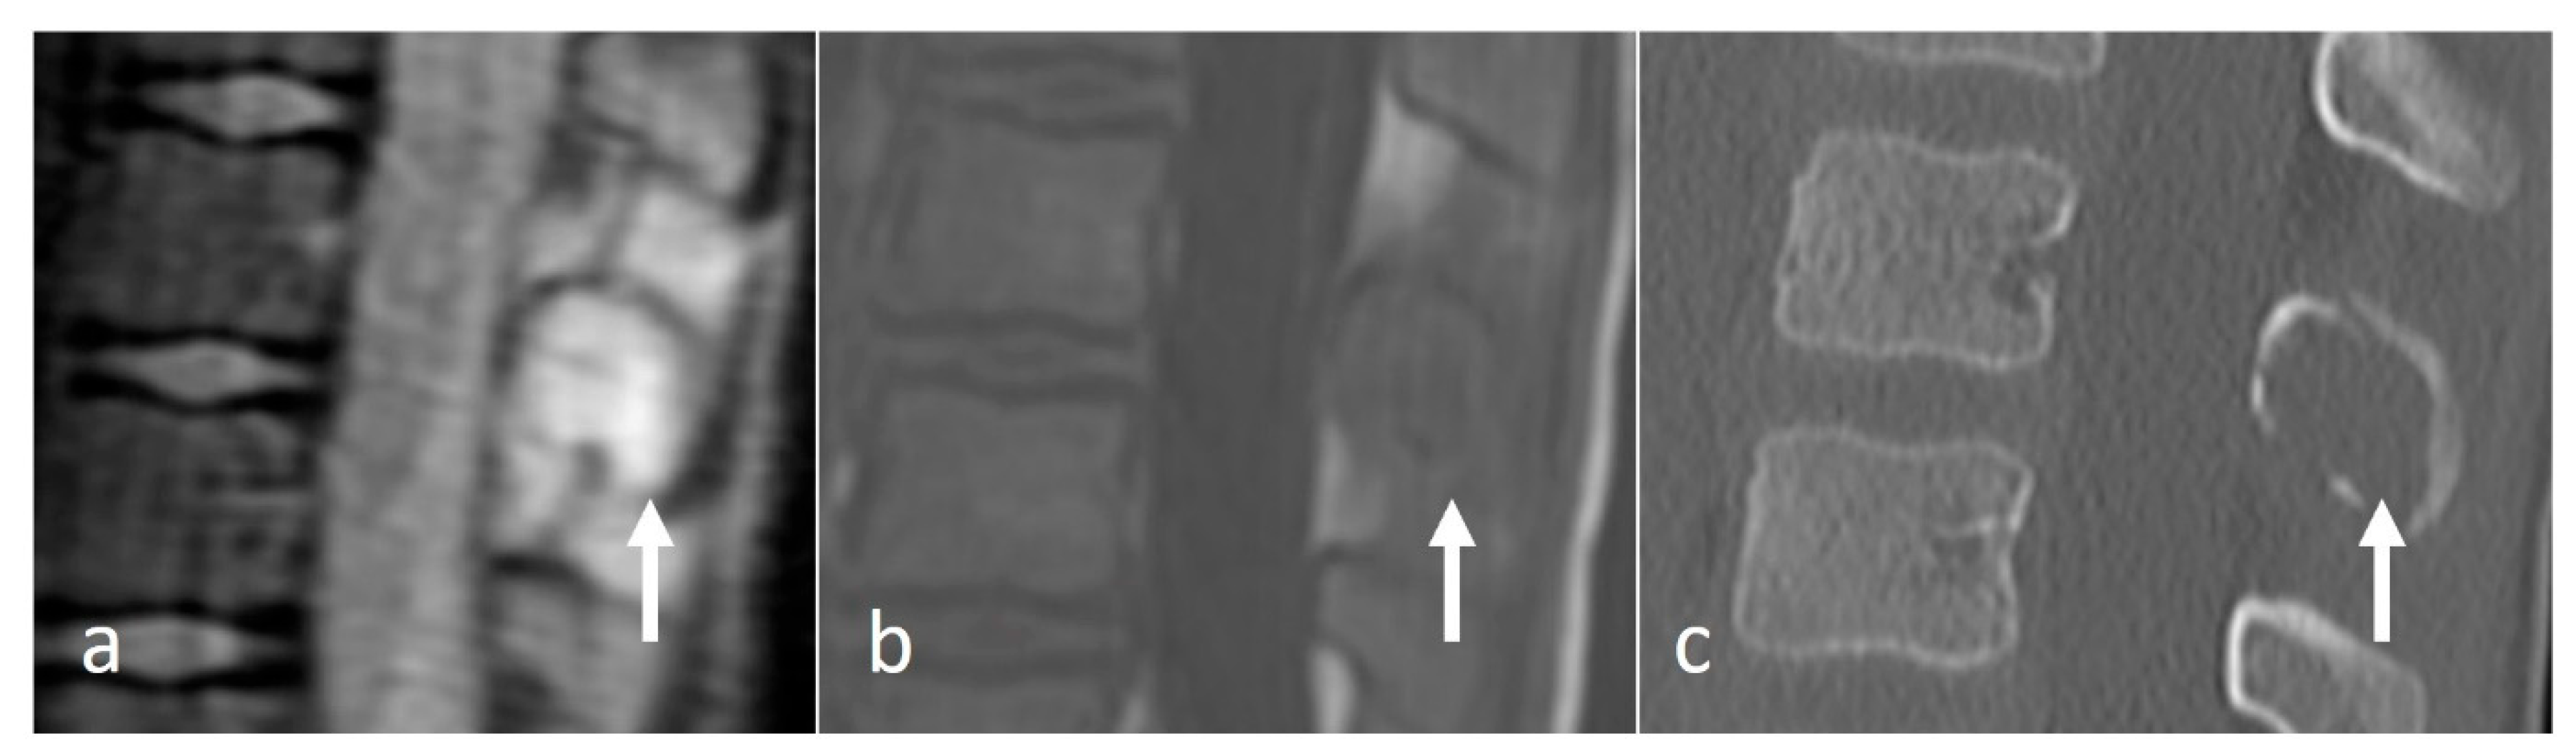

The typical imaging appearance is a well-circumscribed lytic lesion. They can occasionally be expansile and also sclerotic (Figure 6a–c). On MRI, the lesions typically appear as a T1 and T2 hypointense mass, which shows high signal on T2 STIR or T2 fat-saturated images. The lesions enhance after contrast administration [27].

Figure 6.

Sagittal T1 (a), T2 (b) and CT (c) images of a sclerotic myelomatous deposit involving a thoracic spinous process (white arrows). While myeloma typically tends to present as lytic lesions, occasionally they can be expansile and sclerotic as seen here.